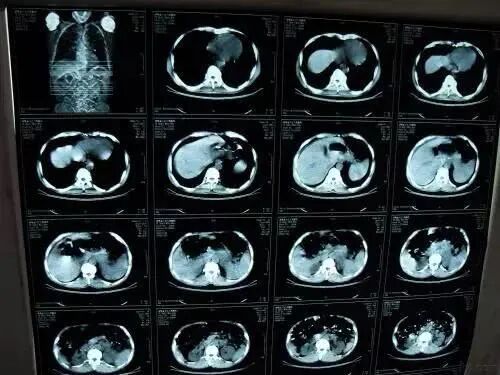

到了医院以后,医生为老邓做了肺部CT检查,发现他的肺部已经长满了恶性肿瘤,是晚期肺癌。